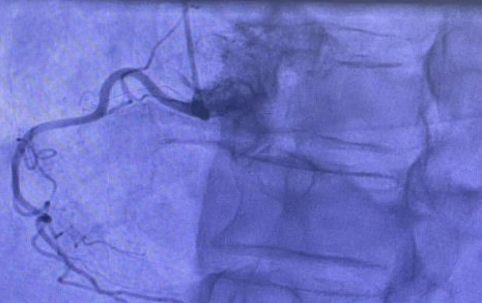

Coronary angiography (Figure 6) confirmed minor disease in one artery but no significant coronary artery disease. Despite this, the cardiac MRI findings were most suggestive of an ischemic aetiology (left circumflex territory myocardial infarction) rather than sarcoidosis.

Figure 6:Coronary angiogram showed focal minor disease in the mid left anterior descending artery (10% stenosis), but was otherwise entirely normal i.e., there was no significant coronary artery disease.